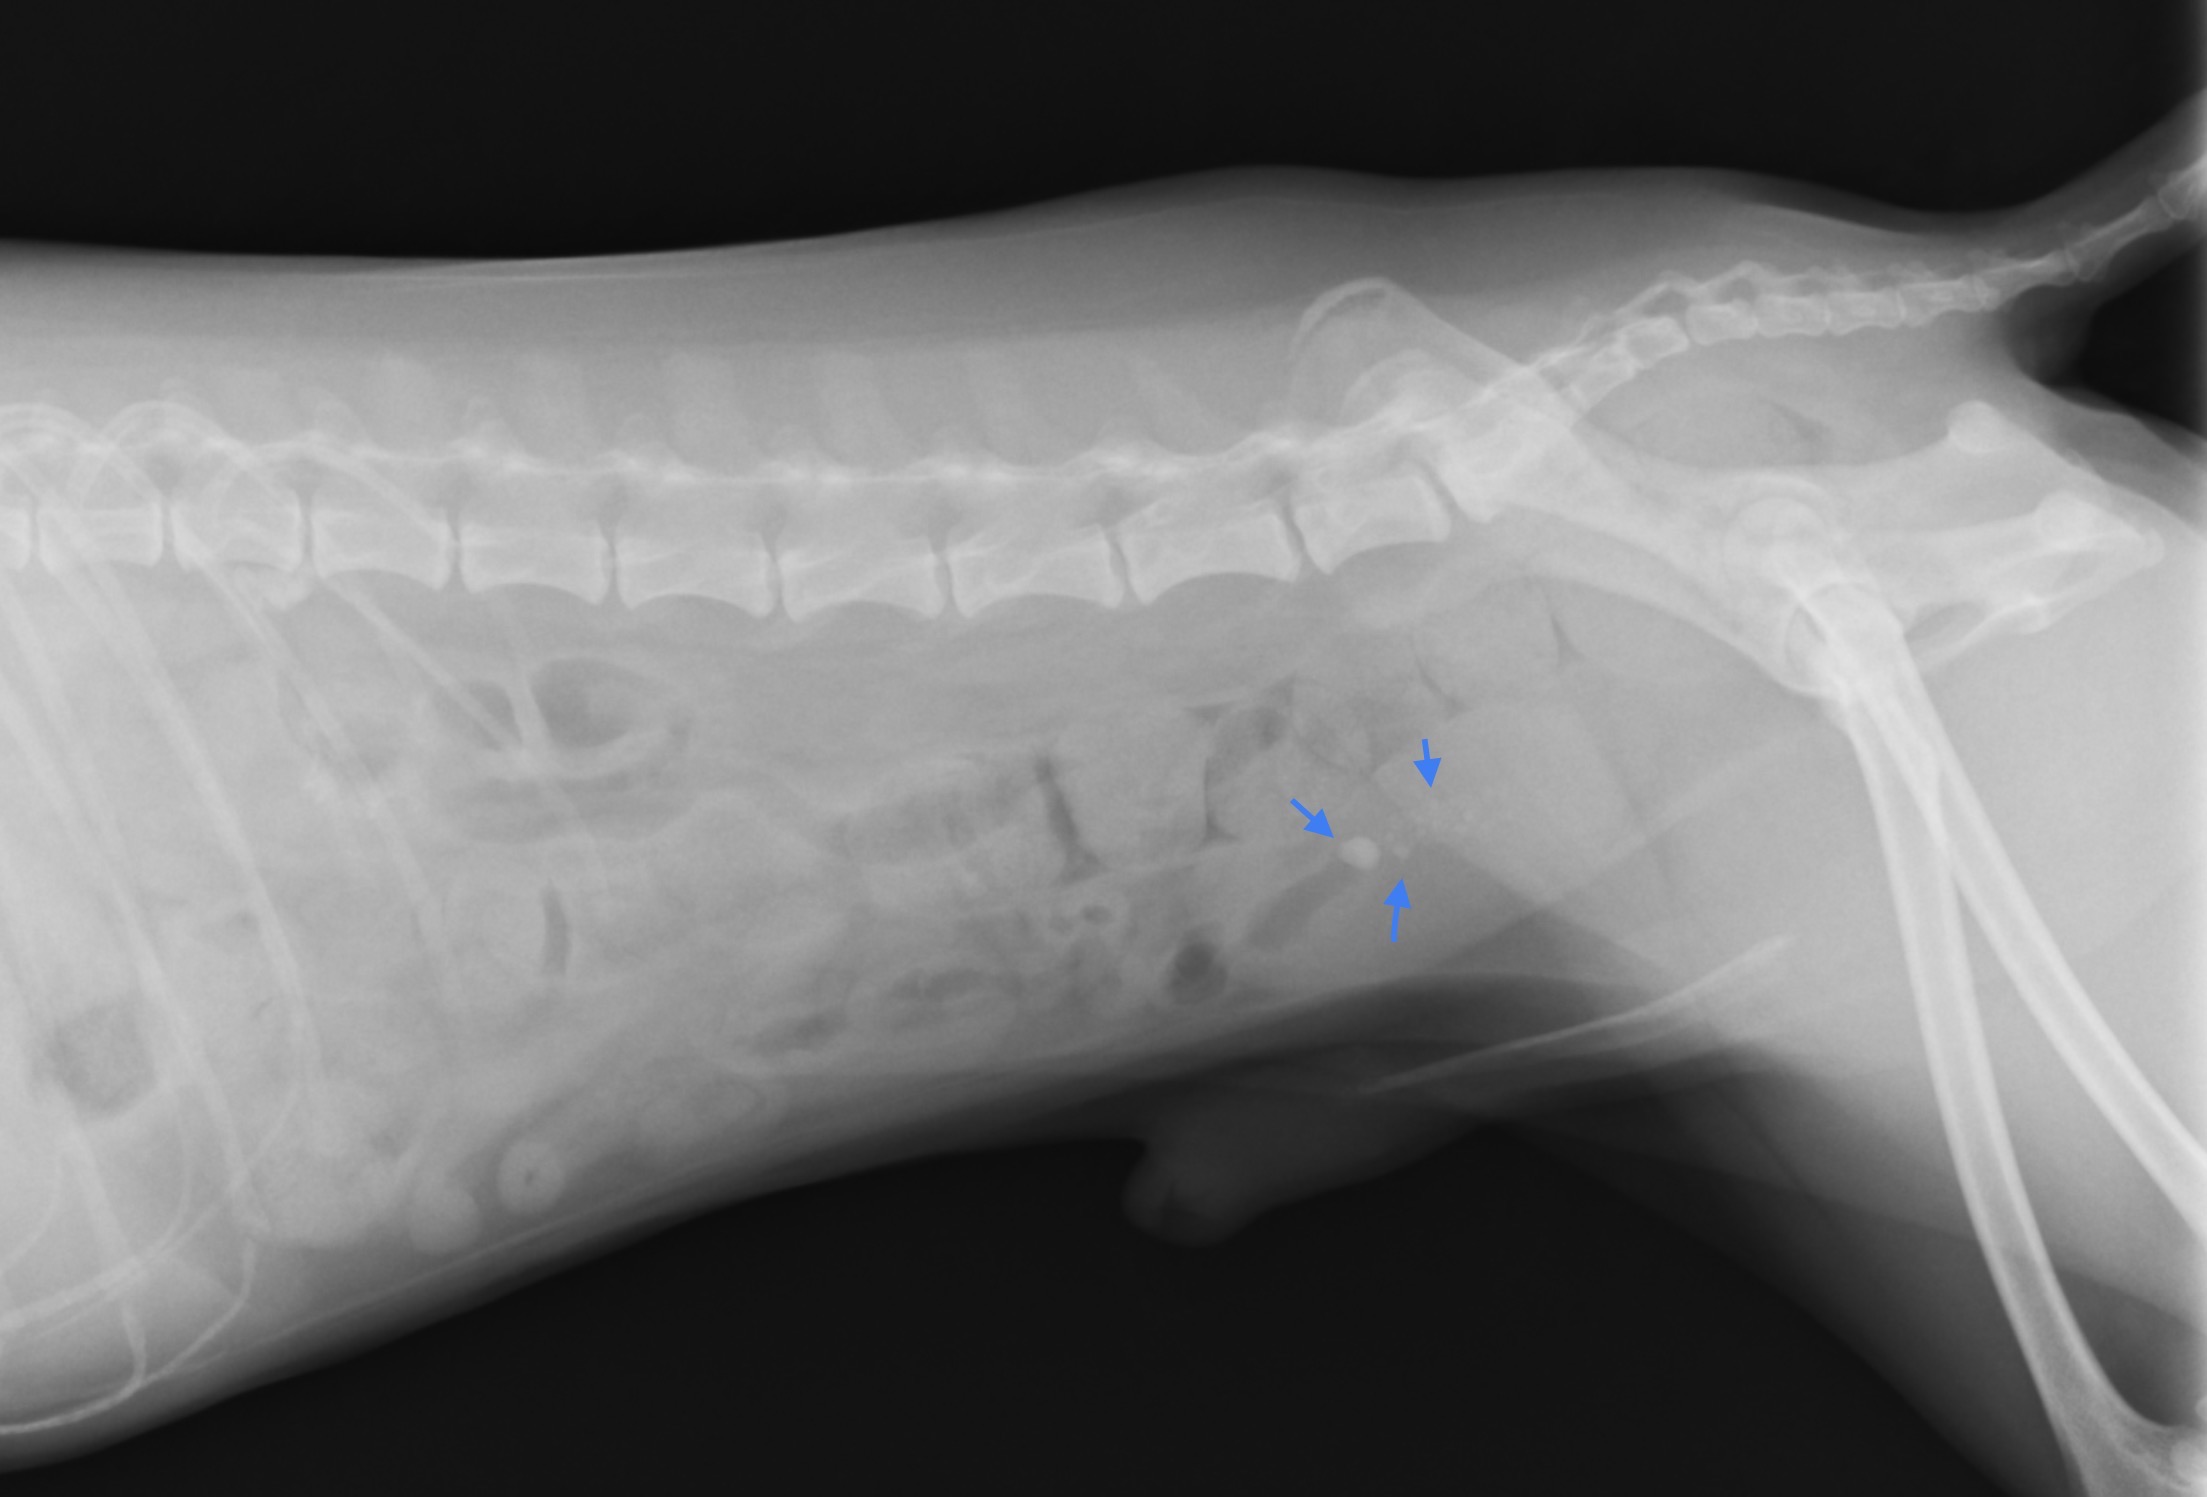

<腹部のレントゲン画像>

矢印で示しているのが膀胱内の結石